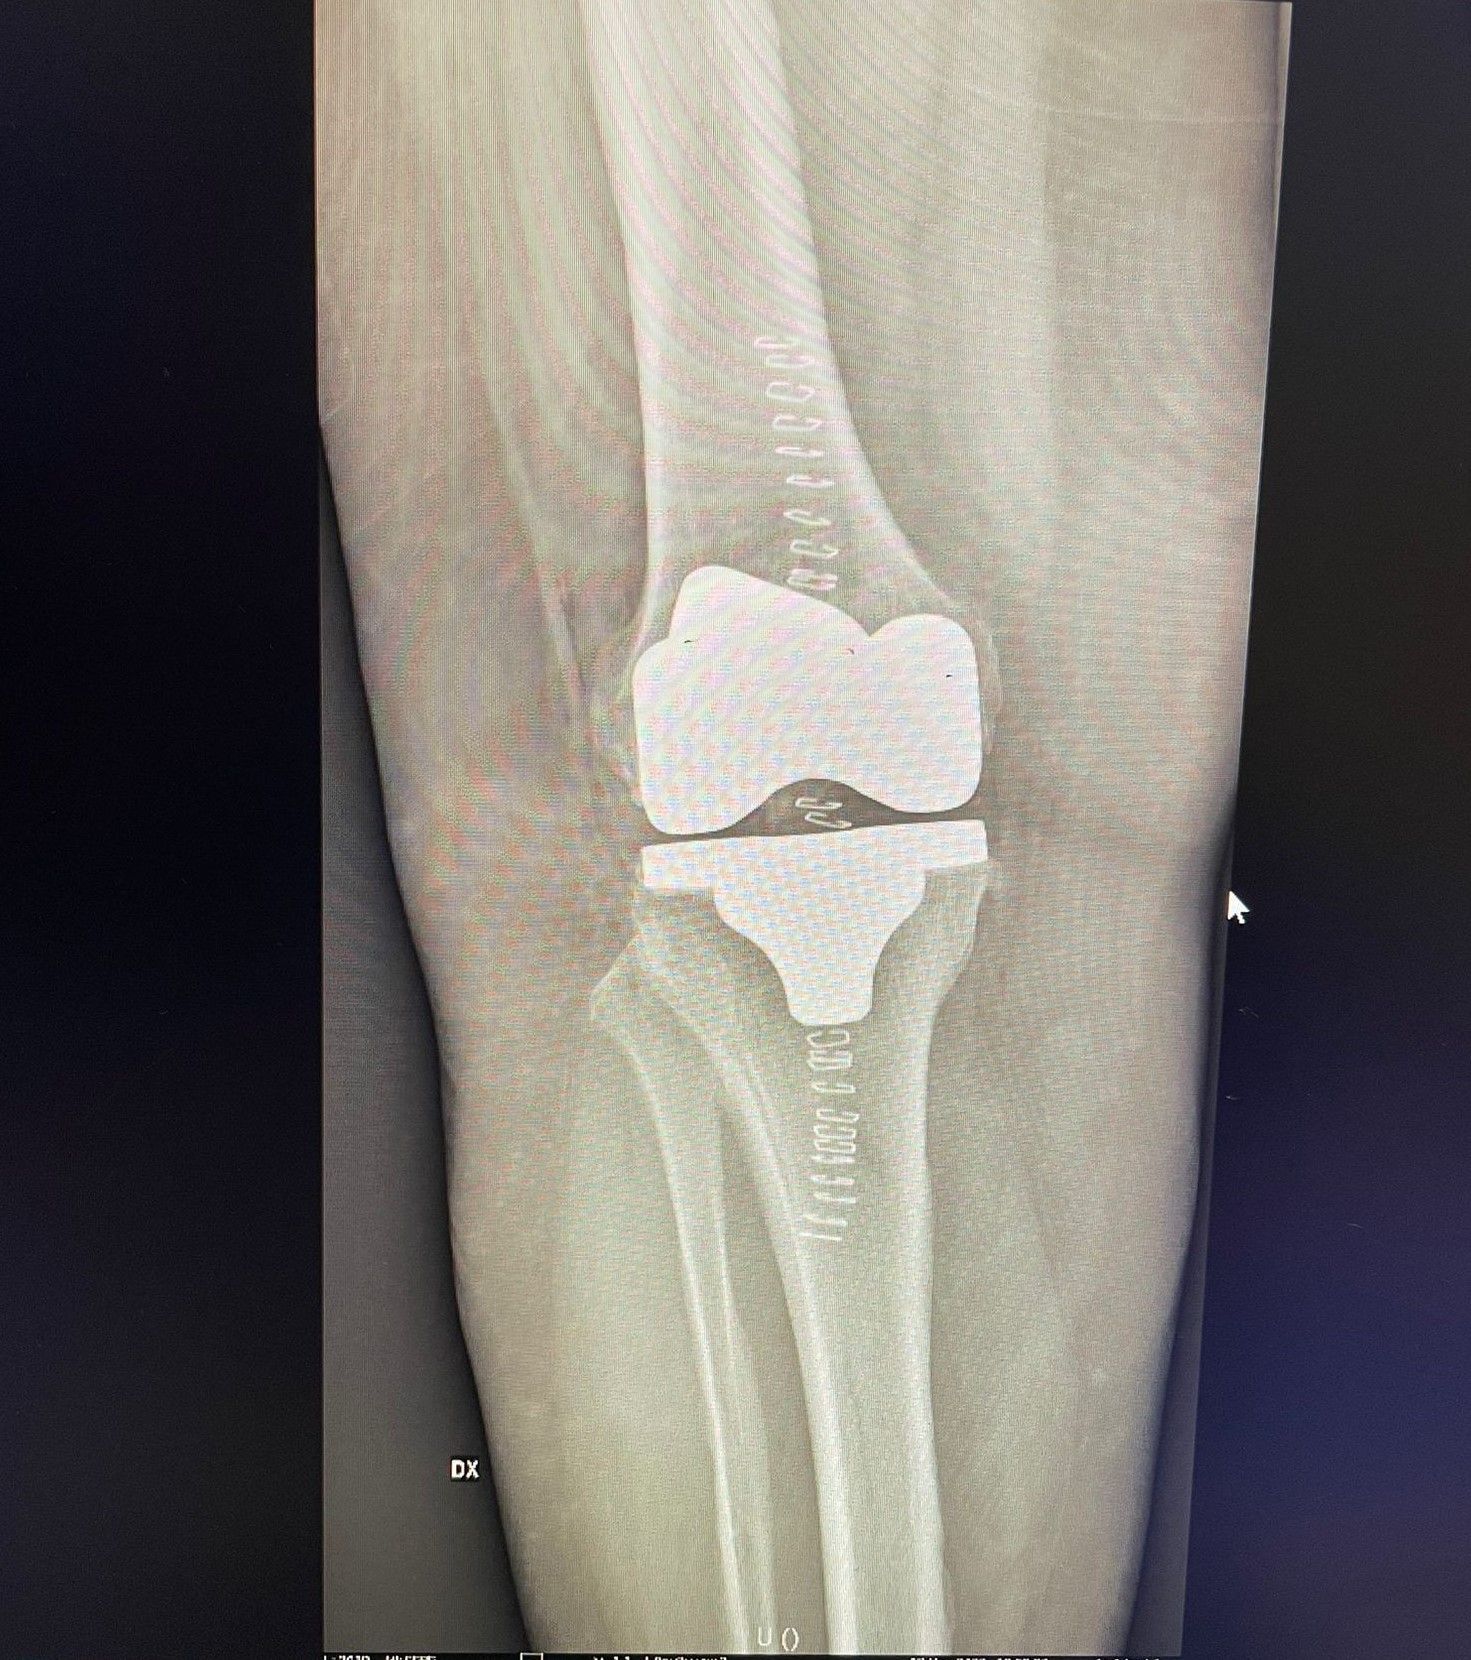

La protesi di ginocchio è costituita da una componente tibiale, una femorale, entrambe in lega di cromo-cobalto, ed un inserto in polietilene che aumenta la congruenza articolare e la stabilità dell’impianto protesico. In genere, le componenti protesiche si fissano all’osso con il cemento, oppure utilizzando degli impianti in tantalio, materiale che si osteointegra completamente entro 3 mesi, senza necessità di cementare.